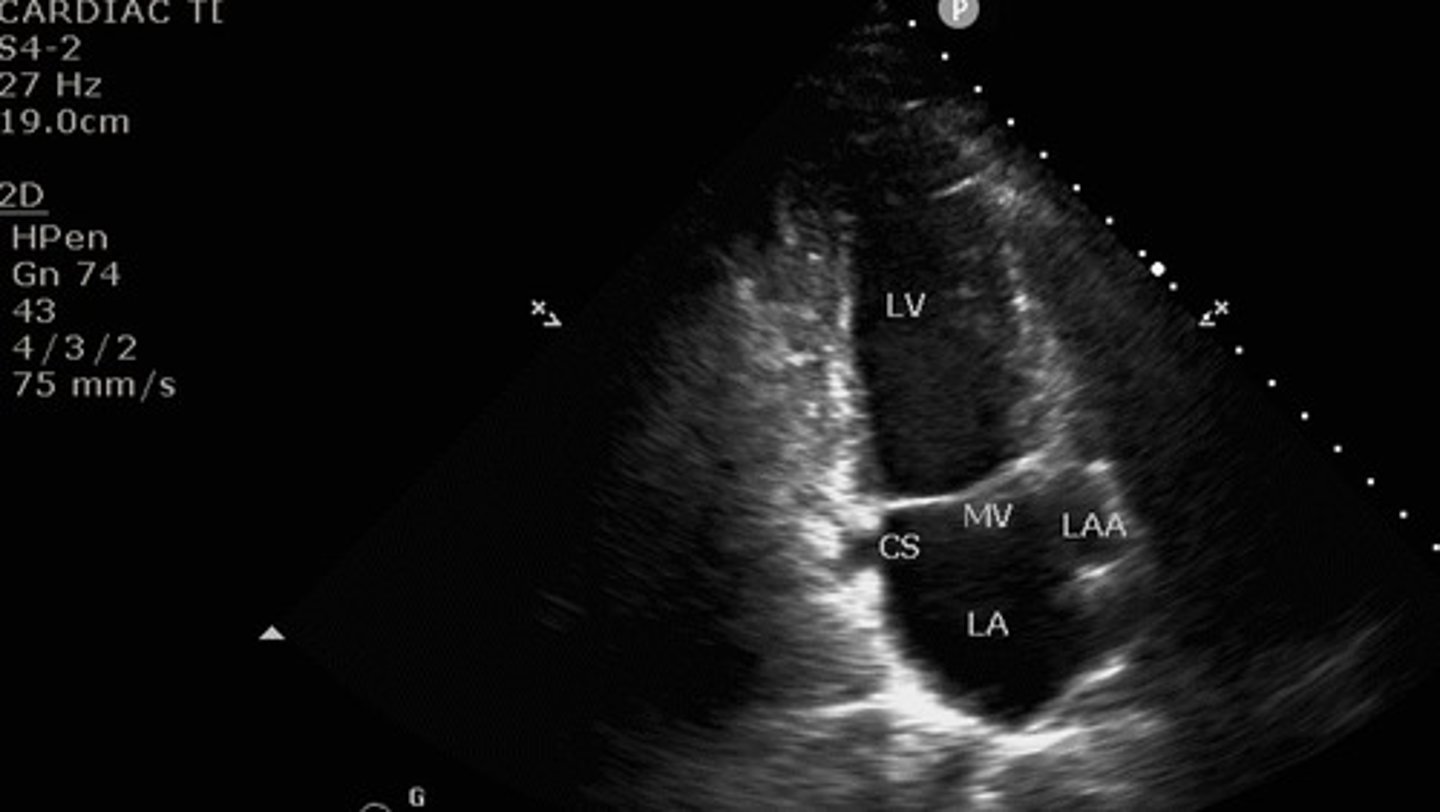

apical 2 chamber view

what view is this

the right side

What side of the heart is omitted from the apical two chamber view?

LV, left atrium, mitral valve

what structures are seen with apical 2 chamber view?